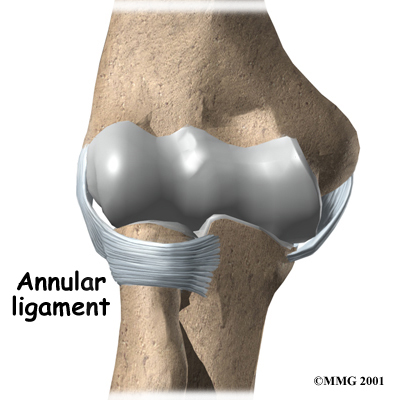

There are several important ligaments in the elbow. Ligaments are soft tissue structures that connect bones to bones. The ligaments around a joint usually combine together to form a joint capsule. A joint capsule is a watertight sac that surrounds a joint and contains lubricating fluid called synovial fluid.

In the elbow, two of the most important ligaments are the medial collateral ligament and the lateral collateral ligament. The medial collateral is on the inside edge of the elbow, and the lateral collateral is on the outside edge. Together these two ligaments connect the humerus to the ulna and radius, and keep the bones tightly in place as they move around the end of the humerus. These ligaments are the main source of stability for the elbow but can be torn when there is an injury or dislocation to the elbow. If they do not heal correctly the elbow can be too loose, or unstable.

There is also an important ligament called the annular ligament that wraps around the radial head and holds it tight against the ulna. The word annular means ring shaped, and the annular ligament forms a ring around the radial head as it holds it in place. This ligament can be torn when the entire elbow or just the radial head is dislocated.